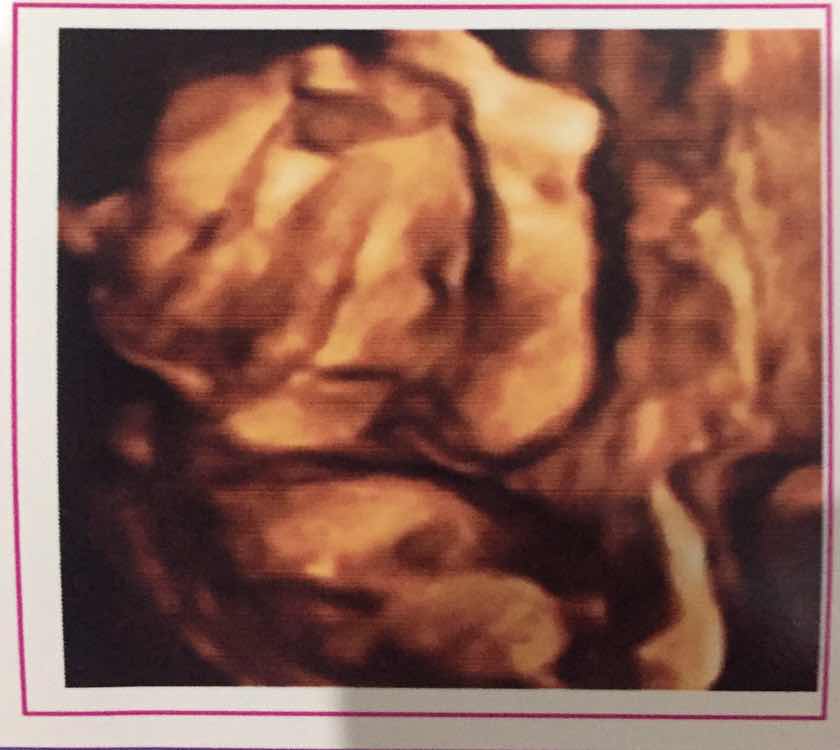

Em mang bầu 22t bị ra những cục giống đậu phụ non có màu xanh mùi hơi tanh khó chịu . Có mom nào từng bị kh ạ , nó có ảnh hưởng đến bé kh và cách chữa làm sao để hết ạ